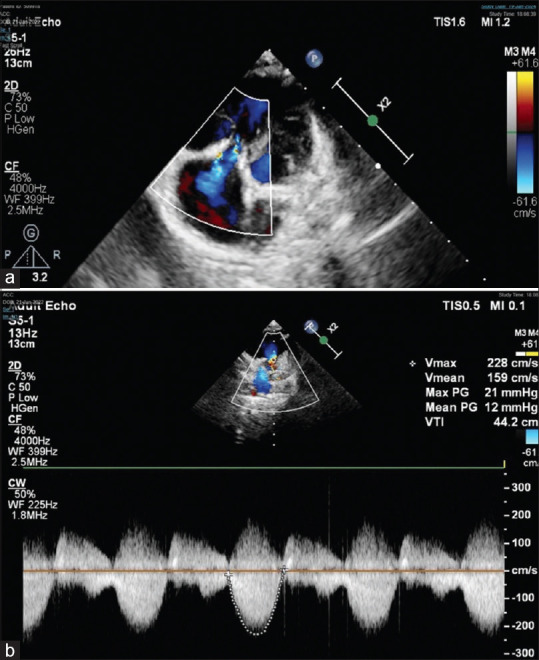

Association of Ebstein's anomaly of tricuspid valve (TV) with tetralogy of Fallot (TOF) is extremely rare. Their coexistence is unique as they modify each other's physiology. We report a case of a girl child having this rare combination along with Diamond-Blackfan syndrome awaiting a bone marrow transplant. She underwent intracardiac repair for TOF along with cone reconstruction of the TV, as tricuspid regurgitation of Ebstein's anomaly would worsen with TOF correction alone. Through this surgery, we aimed to achieve a competent pulmonary valve using a transannular patch with a monocusp and adequate relief of the right ventricular tract obstruction, thus preserving the right ventricular function, as both can affect the repaired TV function in the long term. The child had an uneventful postoperative course and is asymptomatic on follow-up.